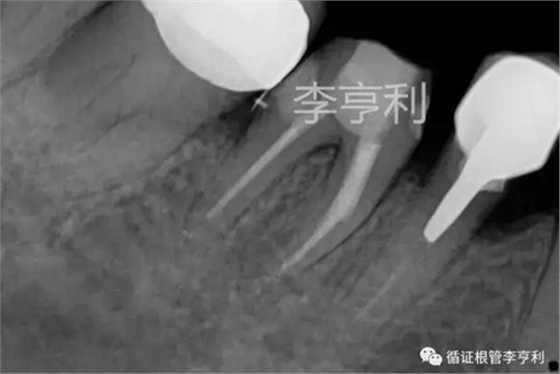

術(shù)前片 (2017-05-16)

輔助檢查:遠中角度投射根尖片,見斷械影像移向近中,故判斷器械分離于近中頰根,根尖周未見明顯異常 。

遠中角度投射,紅色箭頭為分離器械 (2017-05-16)

術(shù)前診斷:46根管已開始治療,根尖周正常組織,伴發(fā)器械分離 (previously initiated treated with normal apical tissues, complicated by separated instrument)。